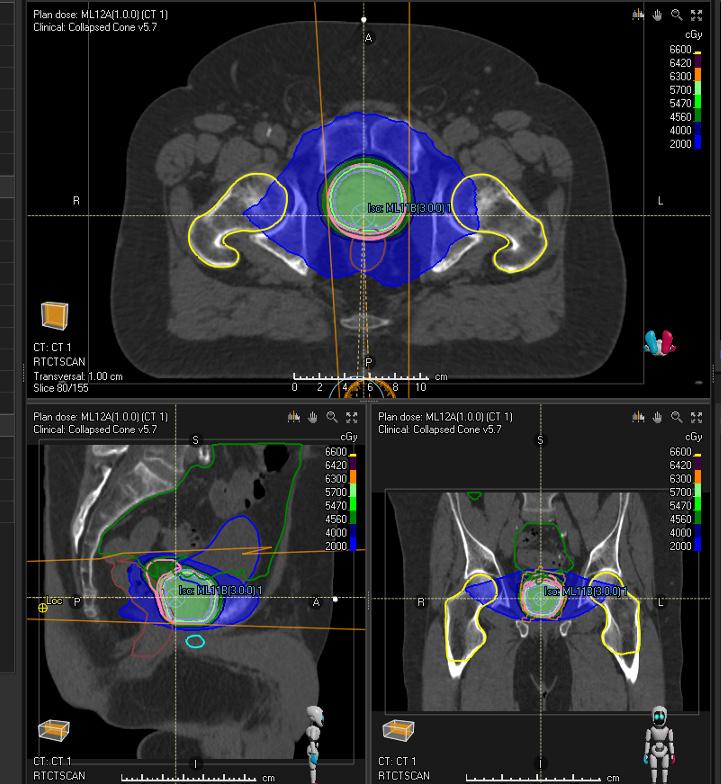

Validation patient example

Treatment site Prostate

Modality Photons

Treatment technique Validated for VMAT

Primary prescription [cGy] 6000

Number of fractions 20

Dose per fraction [cGy] 300

ROI

CTV

PTV

Bladder Wall

Rectal Wall

Femoral Head L/R

Penile Bulb

* Subject to regulatory clearance in some markets. Not for marketing in the USA or Canada.

Clinical goals

At least 6000 cGy dose at 99.0 % volume

At least 5700 cGy dose at 99.0 % volume

At most 6300 cGy dose at 1.0 cm³ volume

At most 30.0 % volume at 4600 cGy dose

At most 50.0 % volume at 3700 cGy dose

At most 5.0 % volume at 4300 cGy dose

At most 5000 cGy average dose

At most 150.0 cm³ volume at 5000 cGy dose